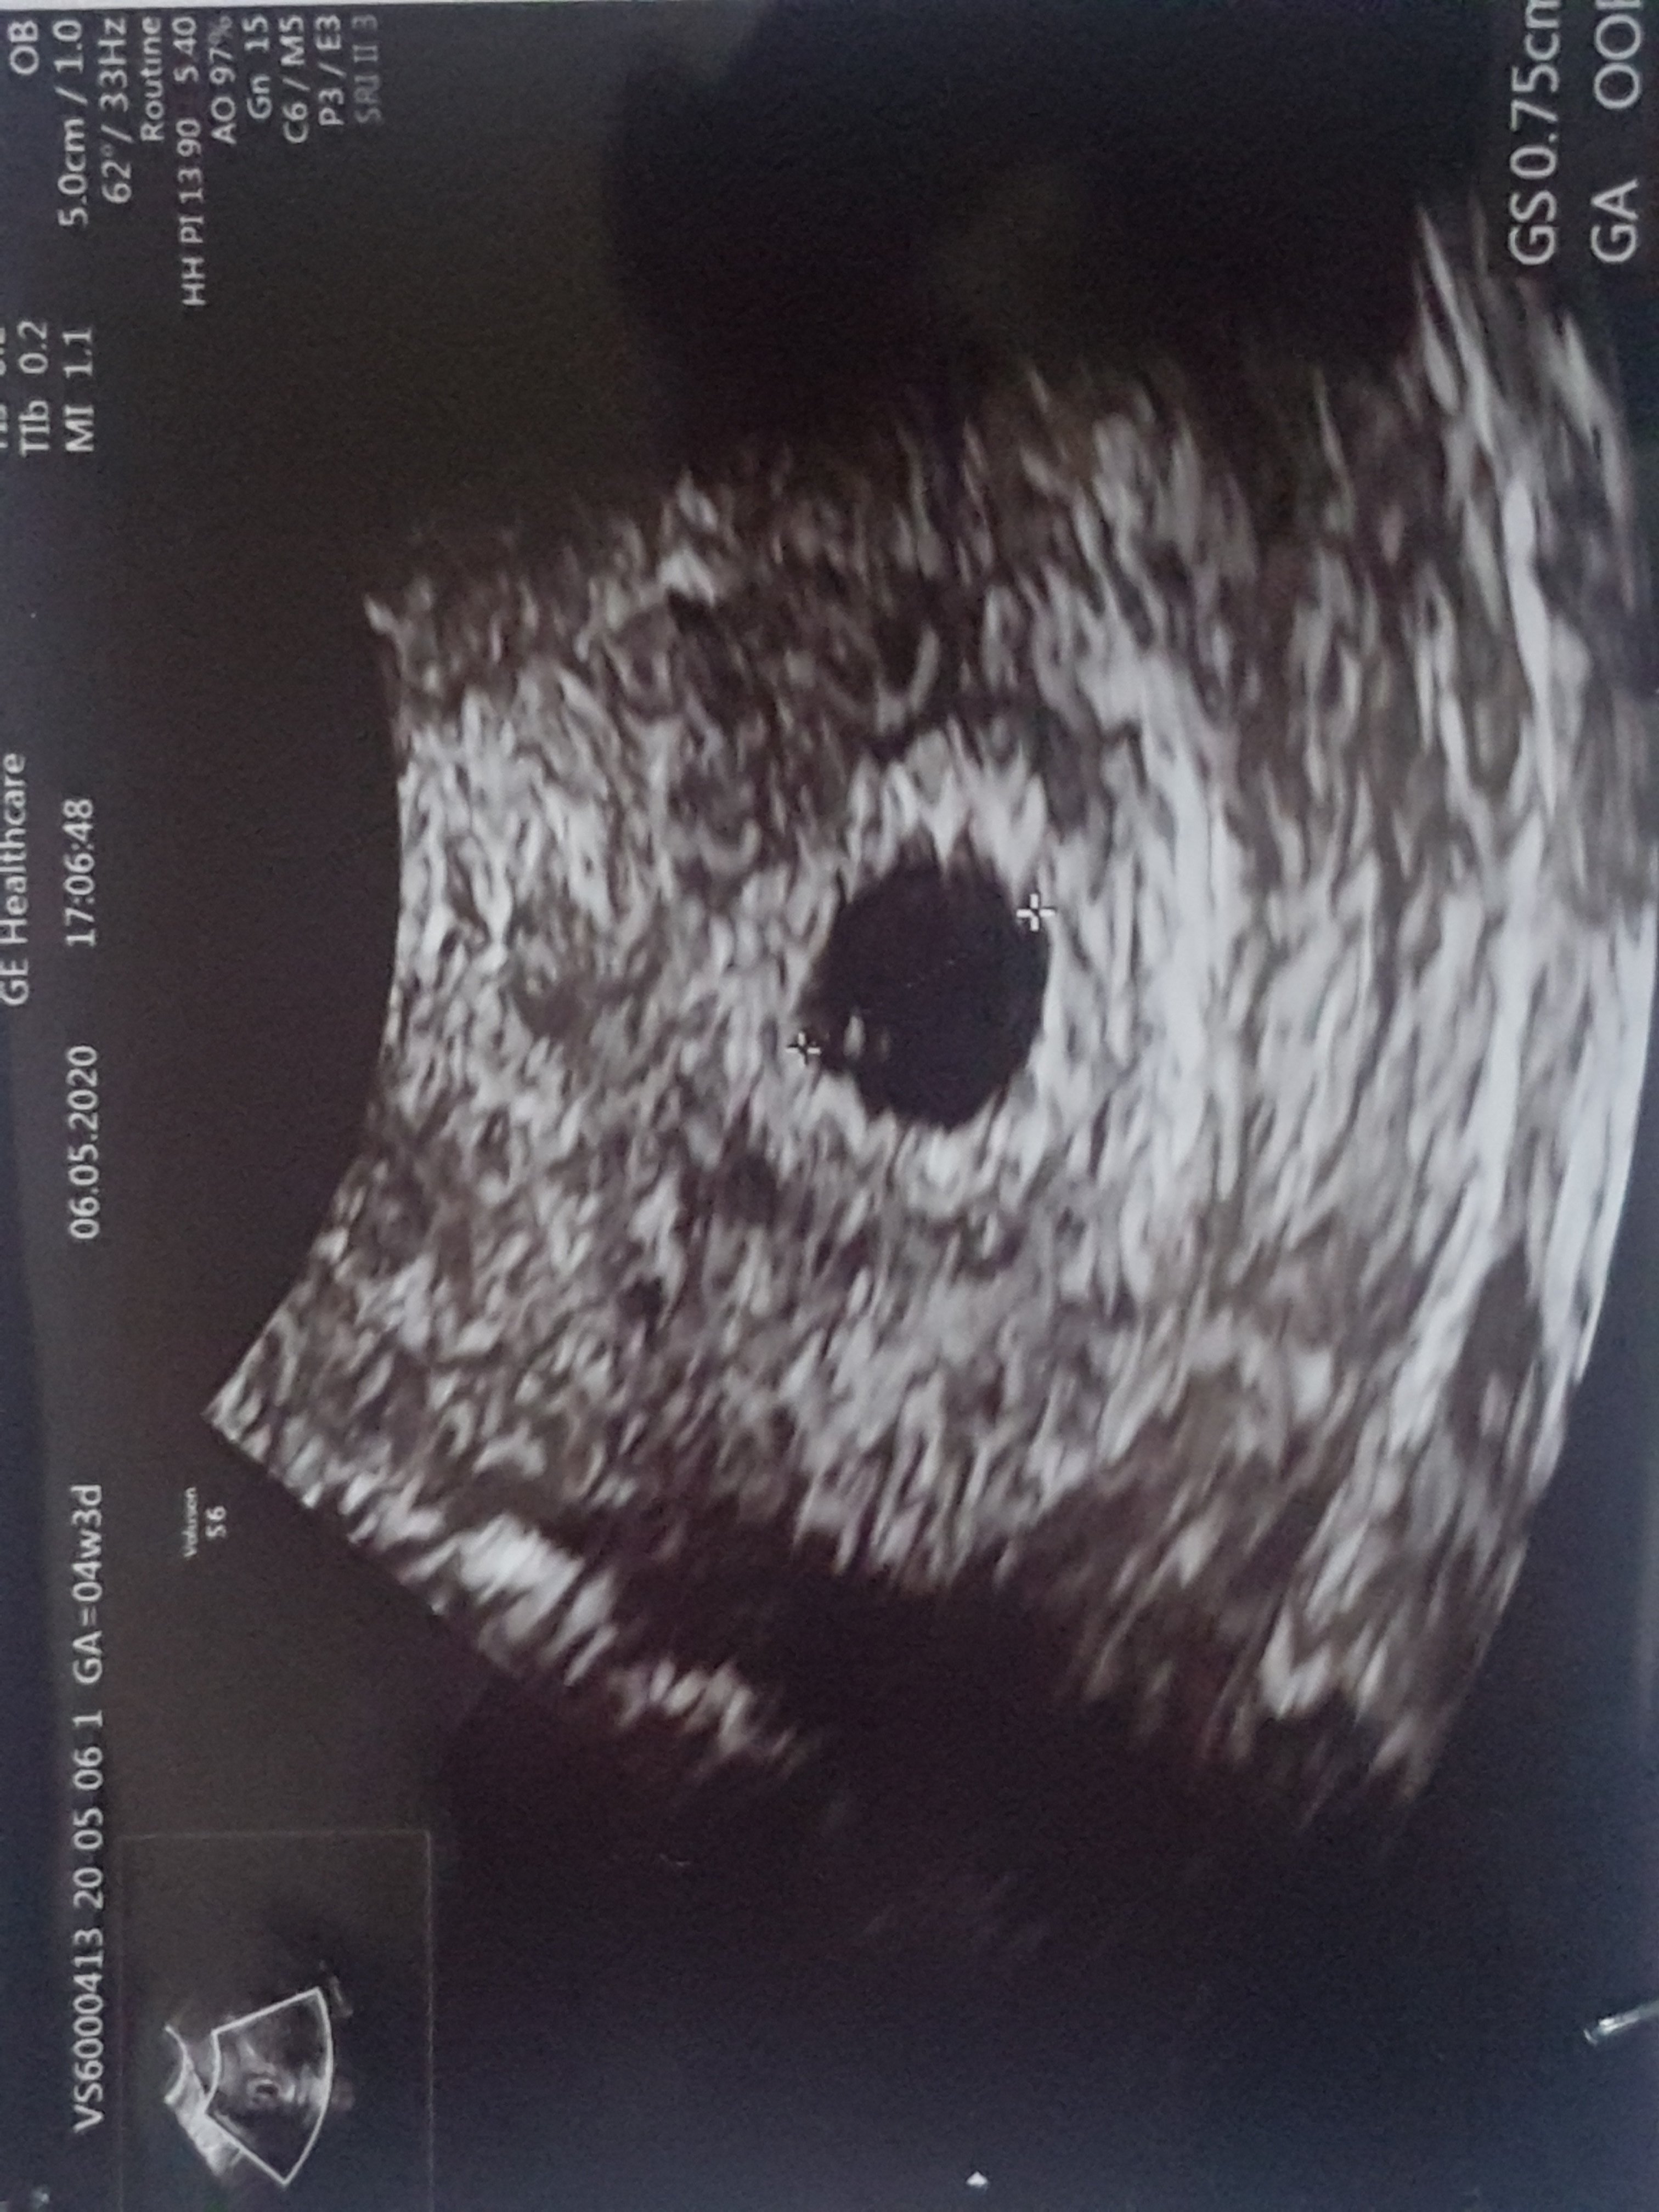

Az sie poplakalam ze zobaczylam ze pecherzyk nie jest pusty![]()

Kochana ten lekarz może nie widział albo nie chciał Ci robić nadzieji. Zdjęcie też jest średniej jakości. Zarodeczek na pewno jest tylko jest maciupeńki i go nie widać aż tak wyraźnieAz sie poplakalam ze zobaczylam ze pecherzyk nie jest pusty![]()